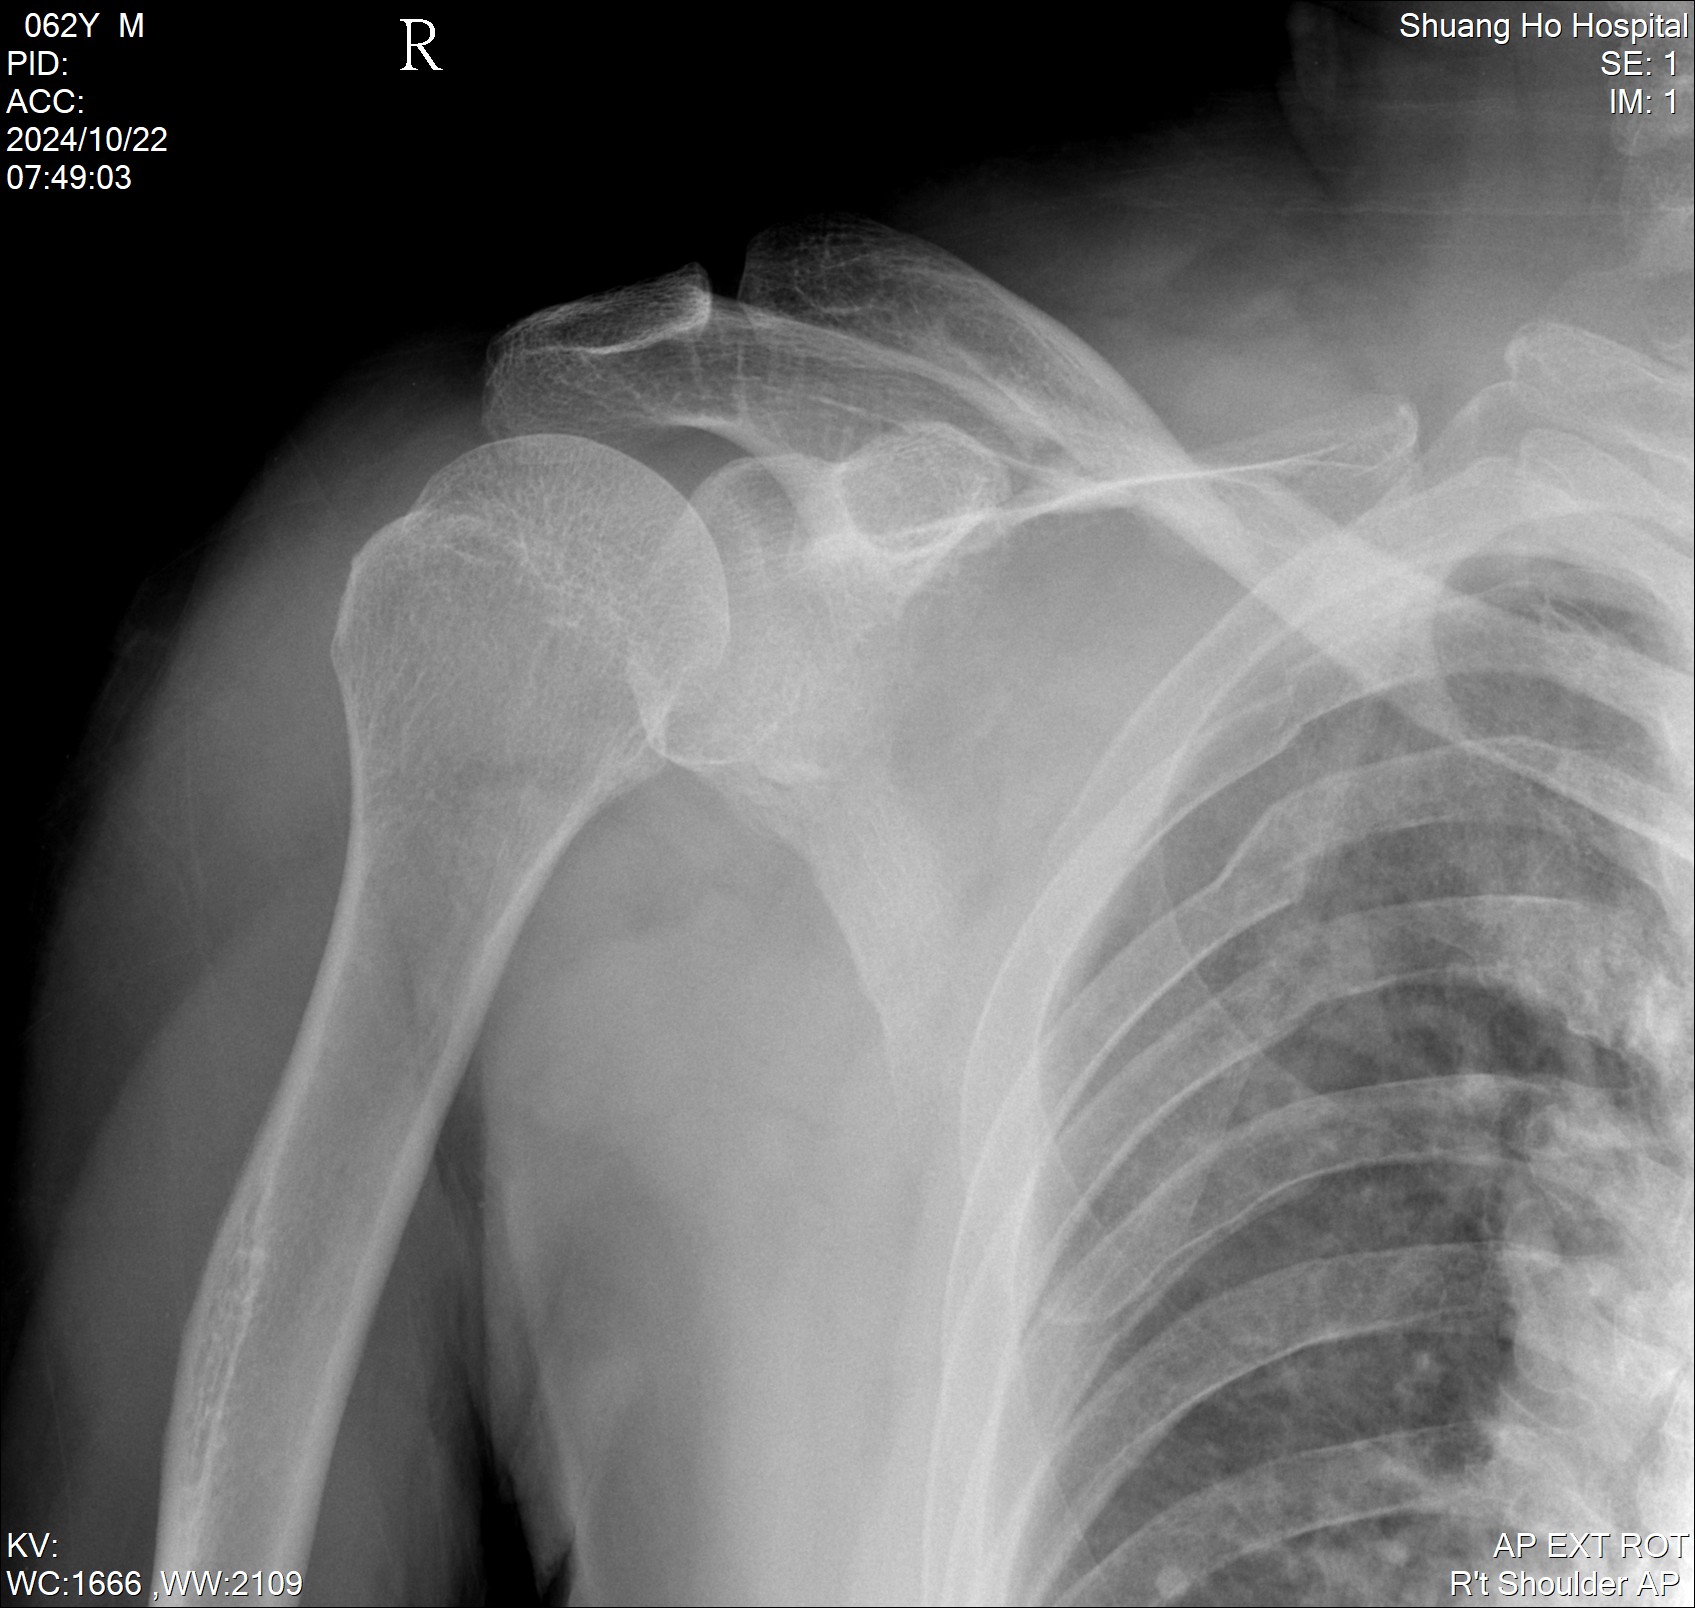

個案62歲男性,車禍,右側鎖骨、多處肋骨及外傷性蜘蛛膜下出血,由於患者右鎖骨及右胸多處處骨折處都嚴重疼痛,在總劑量考量下,選擇先執行SCP block來減輕患者鎖骨處的疼痛 (Numerical Rating Scale (NRS) 9 to 2),後續側身執行Erector spinae plane block。(圖片4、影片4)

圖片462歲男性,車禍,右側鎖骨、多處肋骨及外傷性蜘蛛膜下出血

影片462歲男性,車禍,右側鎖骨、多處肋骨及外傷性蜘蛛膜下出血-SCP block